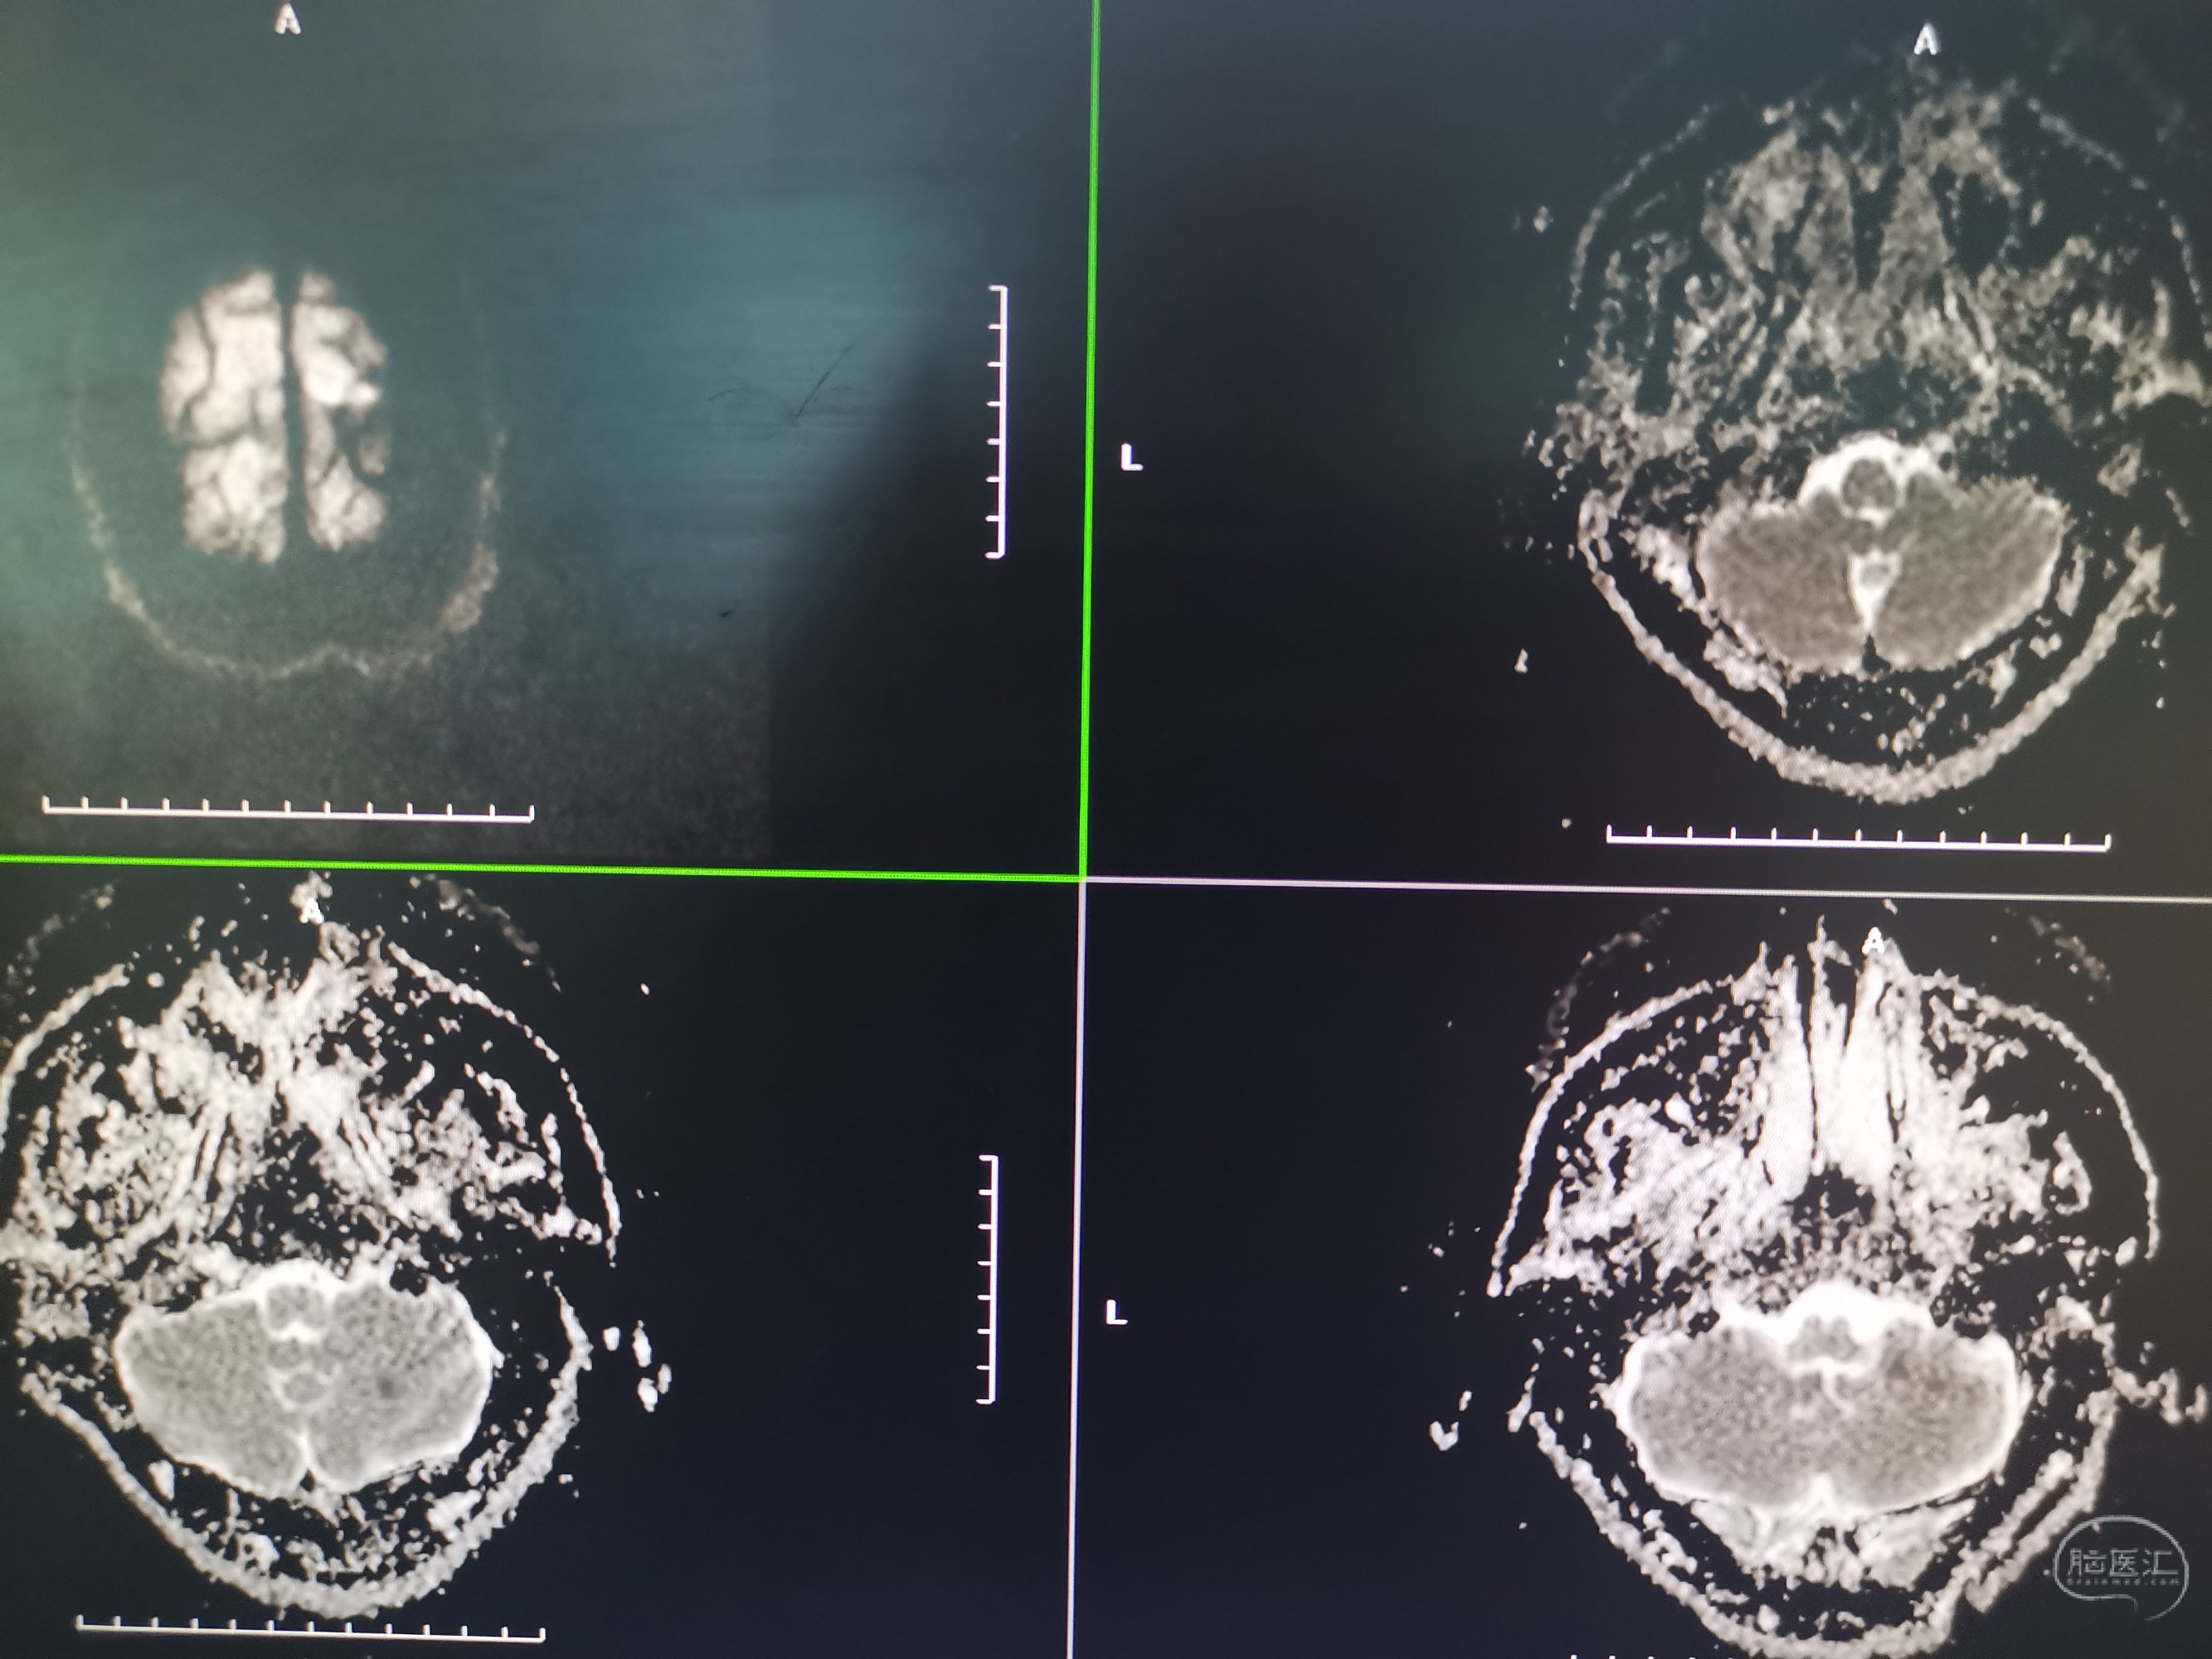

入院MR